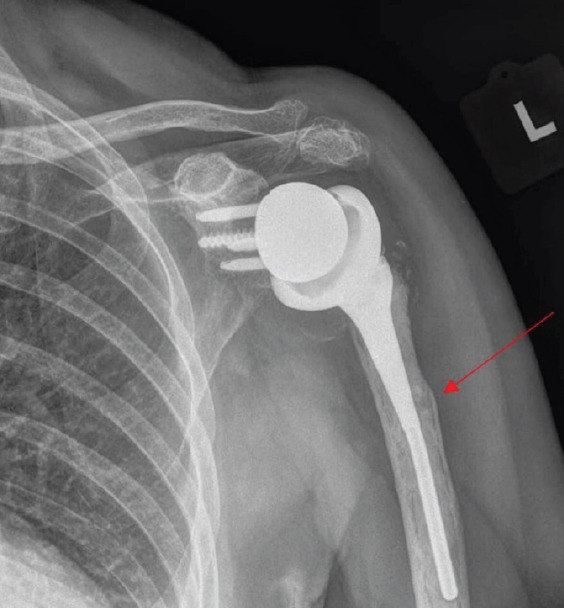

Introduction: Reverse total shoulder arthroplasty (RTSA) is increasingly performed, with a corresponding rise in associated complications such as periprosthetic fractures. Although implant failure and loosening are well documented, deformation of a humeral stem without loosening has not been previously reported.

Case report: A 77-year-old woman, 9 years after an RTSA, presented with left shoulder pain after a fall. Initial radiographs revealed a transverse periprosthetic proximal diaphyseal fracture and a deformed humeral component. She was treated nonoperatively with range-of-motion exercises and pain management. One year later, radiographs confirmed fracture healing, and the patient had no pain and had regained full motion.

Conclusion: This is the first reported case of deformation of a humeral stem in a shoulder arthroplasty. Nonoperative management was successful for fracture healing.